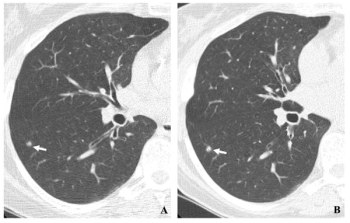

Assessing 20-year follow-up data from a cohort for an international study of annual low-dose CT screening for lung cancer, researchers noted an 81 percent survival rate after an initial primary lung cancer diagnosis for over 1,200 patients with a median 43 pack-year smoking history.

In a newly updated guidance, the American Cancer Society recommends the expansion of annual lung cancer screening with low-dose computed tomography (LDCT) for current or previous smokers 50 to 80 years of age who have a 20-pack-year or greater history of smoking.